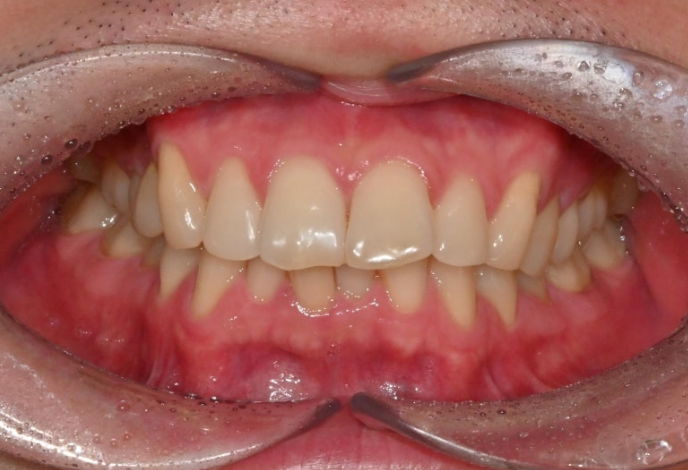

25.12

중심선은 맞아졌으며

어금니 교합은 1급 교합관계를 보입니다.

앞니 뻗침은 좋아졌네요.

이제 전후 비교 보겠습니다.

과개교합의 개선으로 아래앞니가 온전히 보이게 되었습니다.